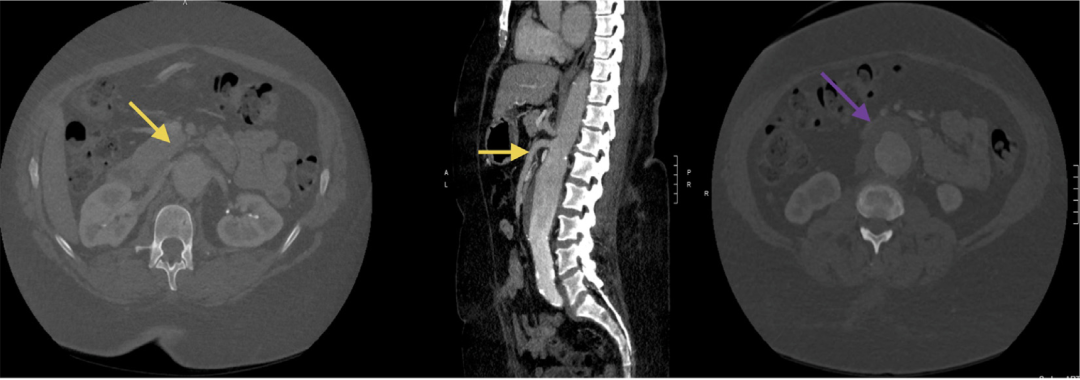

术前横断面影像学检查显示一例5.5厘米IV型胸腹主动脉瘤;黄色箭头在轴位和矢状位图像上指向瘤体延伸至内脏血管水平,紫色箭头在轴位图像上指向瘤囊内存在血栓的动脉瘤。